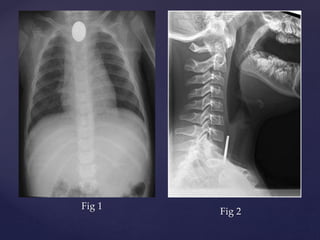

Fig 1

Fig 2

{ {

 Plain X Ray neck ,

chest and abdomen

AP view.

 Showing a round

radio opaque foreign

body in the

esophagus.

 Probably a coin.

 Plain X Ray neck

Lateral view.

 Showing edge on

view in lateral view

suggesting of FB in

oesophagus (in

contrast to FB

trachea)

Foreign Body Oesophagus (Coin)